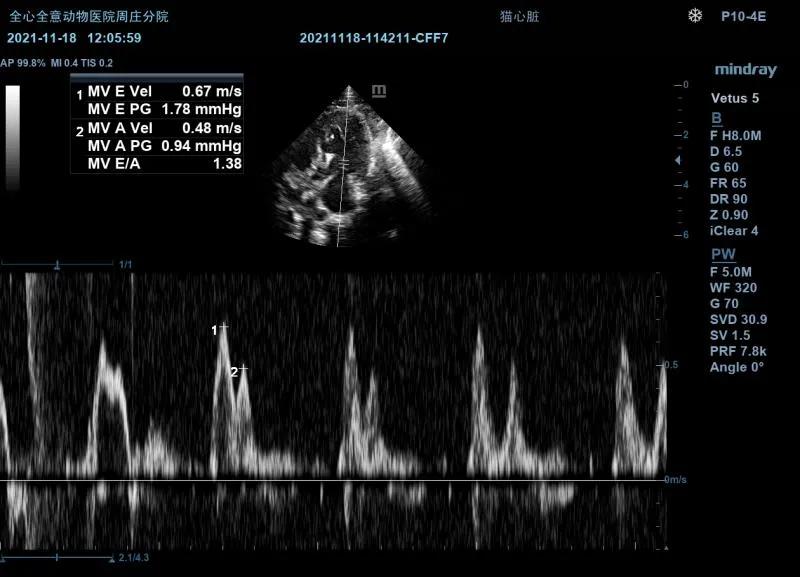

超声检查:

左侧心尖四腔(color):

可见收缩期二间瓣反流信号。